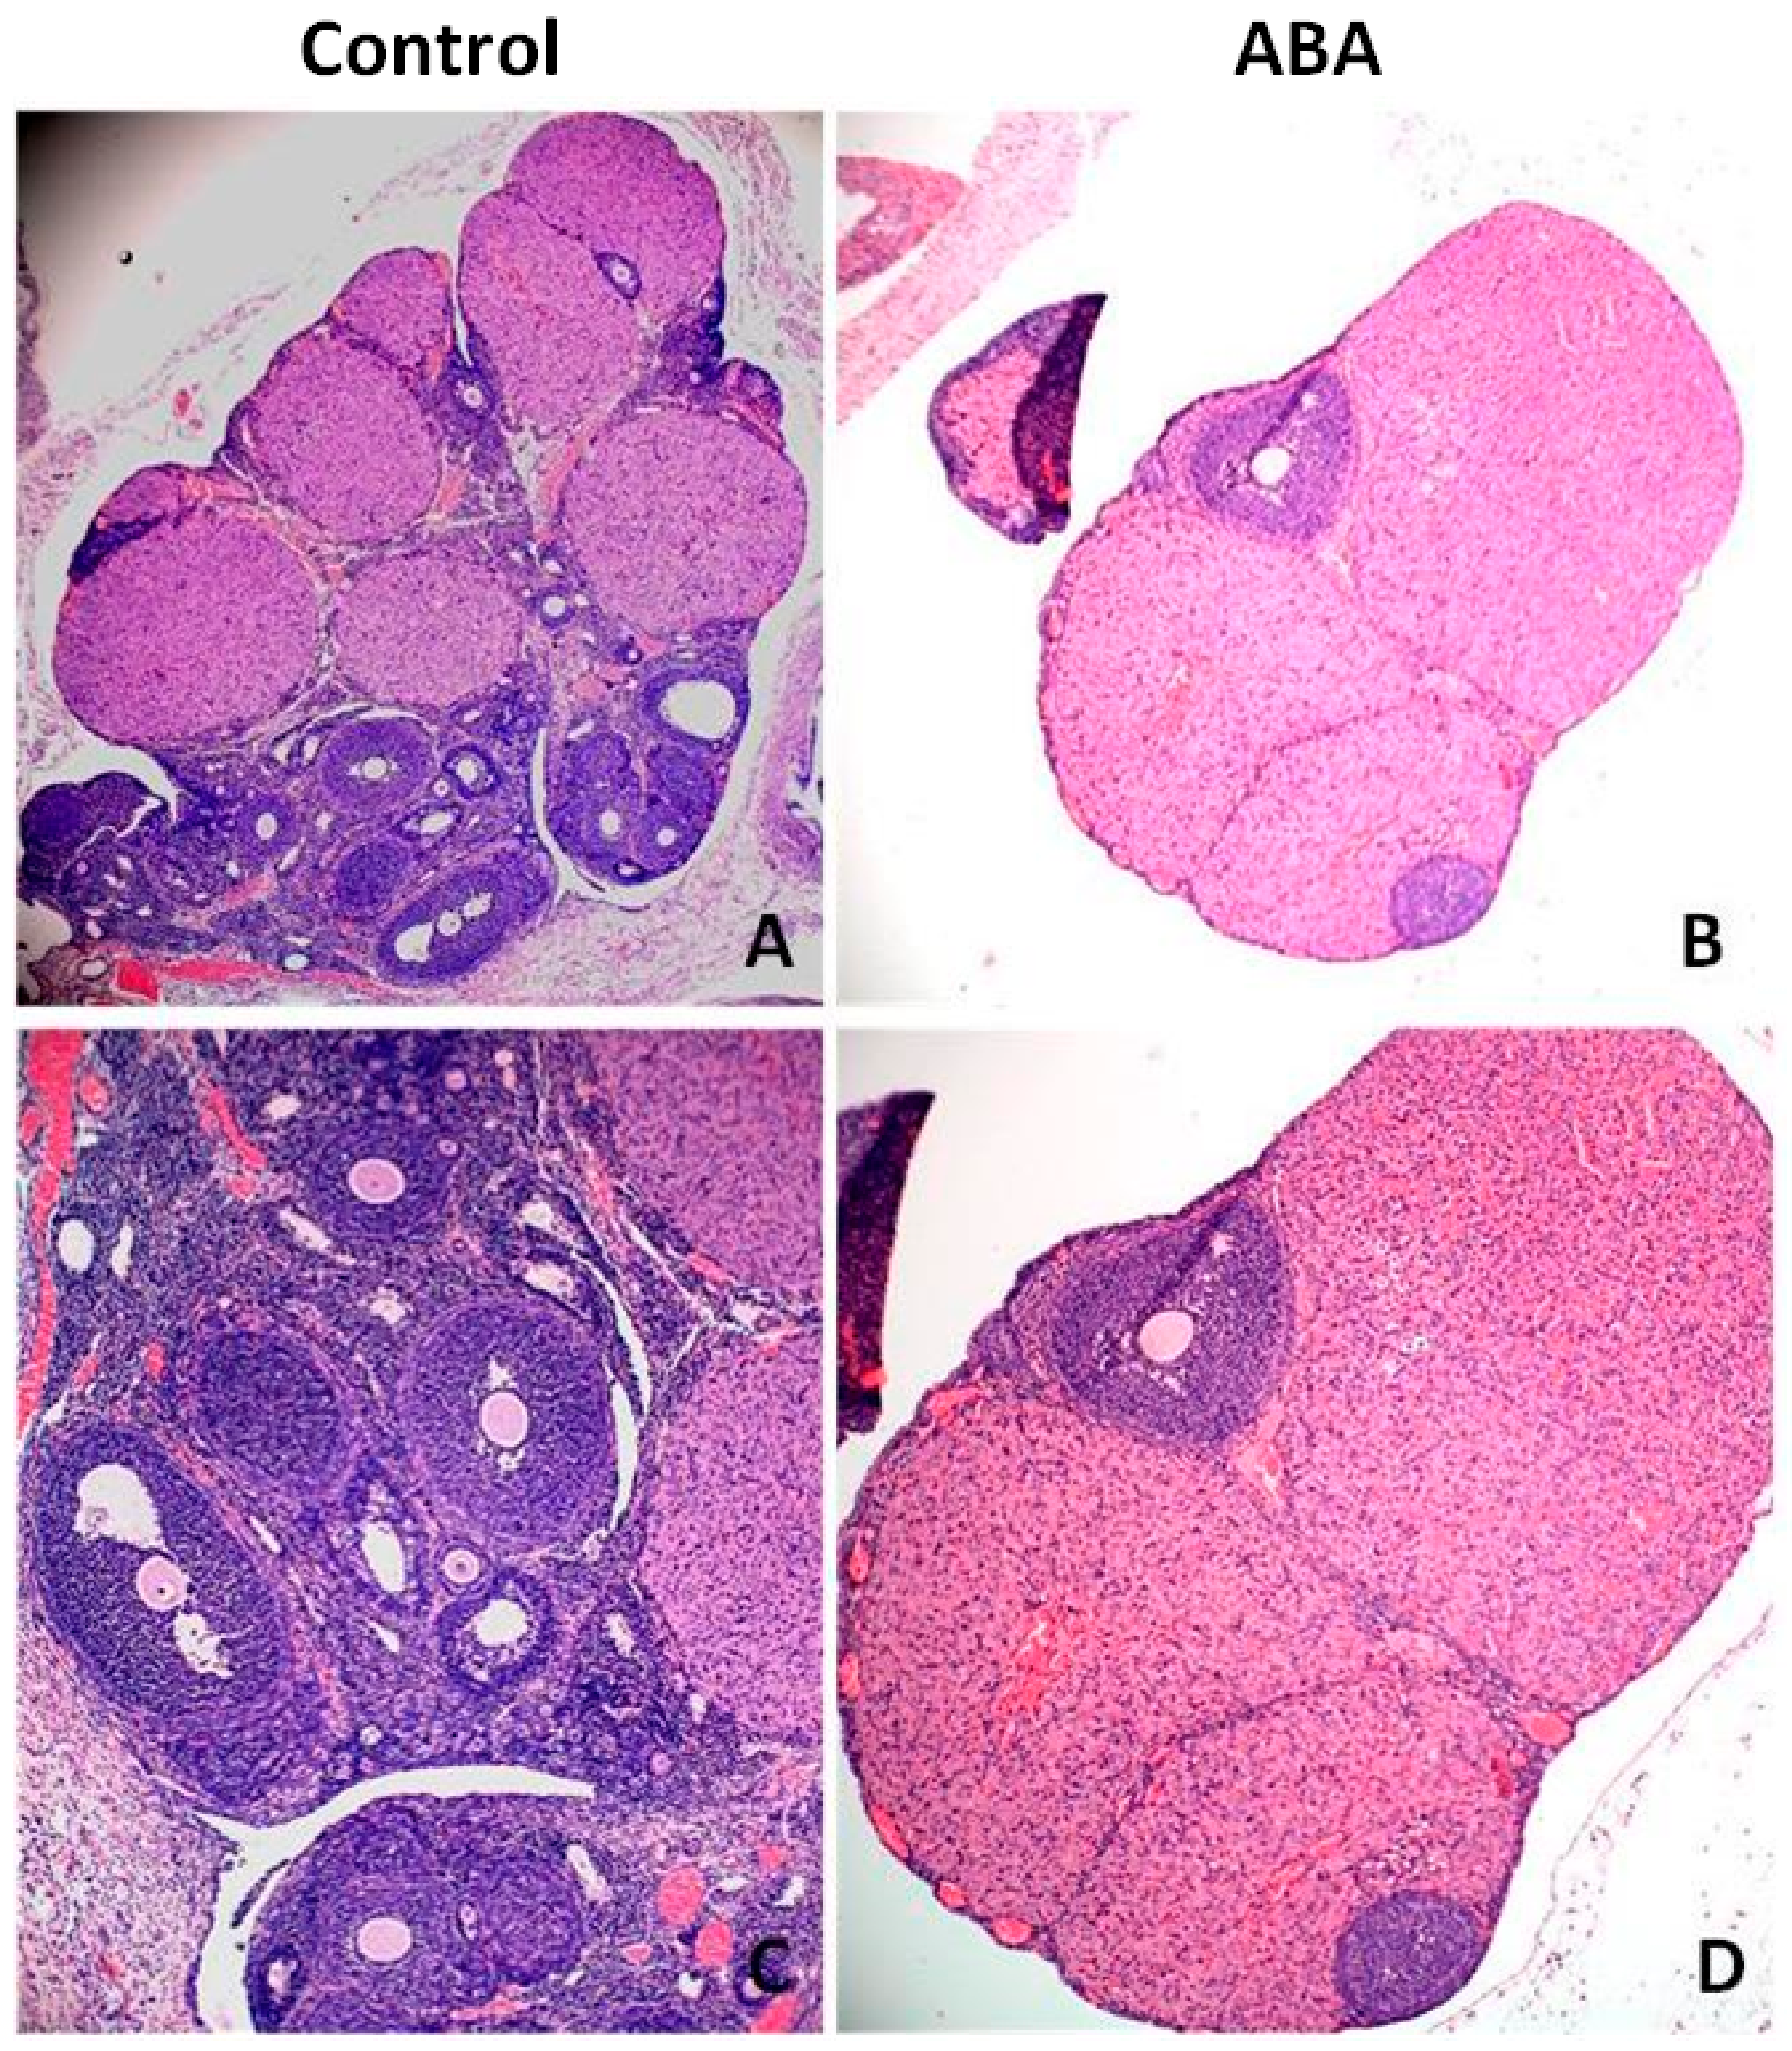

Microscopic analysis of ovarian tissue revealed a reduction in the number of antral follicles (Figure 8). The ovaries of healthy rats contained more follicles at various stages of growth, including the dominant follicle, while the ovaries from the ABA group had a poor pool of follicles without a leading follicle. The expression of Inhibin B was significantly higher in the ABA group (Figure 9).

Figure 9.

Hematoxylin–eosin-stained cross sections of rat’s ovaries with antral follicles in the control group (A,C) and ABA group (B,D). The ABA group is characterized by a poor follicle pool; only a few follicles were observed in the marginal part of ovaries. Total magnification: 40× (A,B); 100× (C,D).